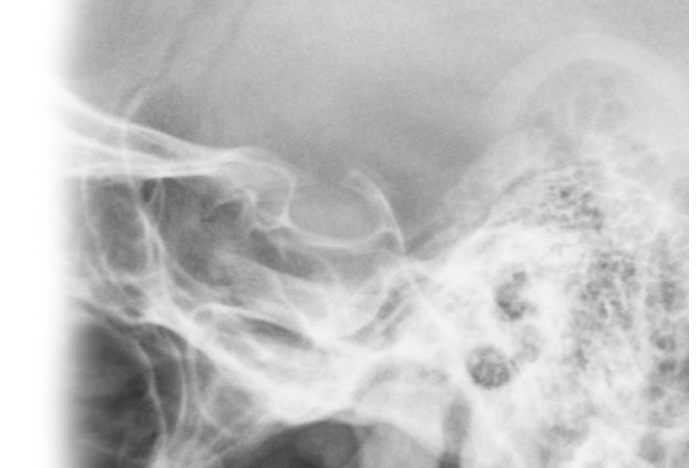

Рентгенография турецкого седла Рентгенография турецкого седла

Рентгенография турецкого седла

Рентген турецкого седла - важный метод исследования, который позволяет получить детальное изображение области турецкого седла головного мозга.